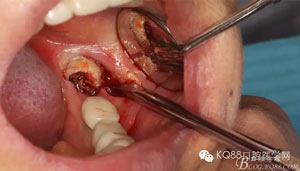

圖5.頰側(cè)做微切口、翻瓣,暴露頰側(cè)38牙體及頰側(cè)骨板。

圖6. 微創(chuàng)丫挺增隙